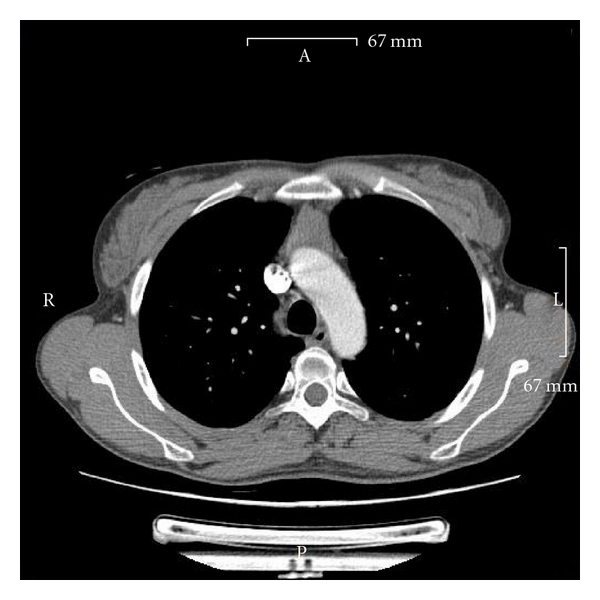

Contrast-enhanced chest CT scan due to worsening dyspnoea in October 2009 revealed an enlargement of the mediastinum (Figure 1). Radiologically, the enlarged mediastinal mass was highly suspicious of a thymoma or mediastinal posttransplant lymphoma. Clinical laboratory parameters (blood count, LDH, immunoglobulins, and virus titres) were all within the normal range.

Due to the large size of the mediastinal mass, a total thymectomy via hemisternotomy was performed in November 2009.